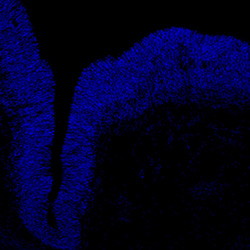

DAPI

6PCW human midbrain